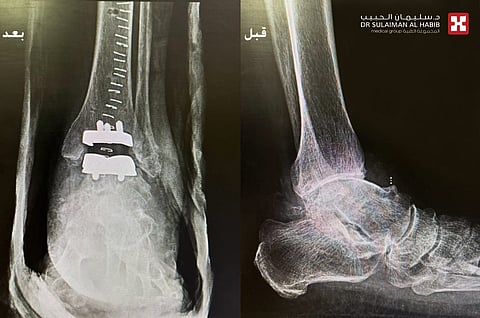

وأوضح الدكتور عرفان أنه عند إجراء الفحص السريري للمريض والسماع لشكواه ودراسة تاريخه المرضي، تبين أنه أجرى سابقاً عملية تثبيت للكاحل الأيمن بمستشفى آخر، وأراد أن يجري نفس العملية بالمفصل الأيسر، وبعد إخضاعه لفحوصات دقيقة بالأشعة السينية والمقطعية (C.T. Scan)، اتضح وجود خشونة شديدة من الدرجة الرابعة بالكاحل الأيسر مع إنحراف بزاوية المفصل، وبعد اجتماع الفريق الطبي تم اتخاذ القرار بالتدخل الجراحي.

مشيراً إلى أن العملية استغرقت 3 ساعات تحت التخدير العام، وتم فيها البدء بإجراء معالجة للخشونه تبع ذلك تعديل إنحراف زاوية المفصل، ومن ثم تركيب تغليف لمفصل الكاحل الأيسر، نقل بعدها المريض لجناح التنويم، وتبين من مؤشراته الحيوية خلال أول 24 ساعة من الإجراء الطبي تحسن حالته الصحية، وبدأ في الوقوف والحركة بمساعدة العلاج الطبيعي، وفي اليوم الثاني استطاع المشي والحركة بأريحية ولله الحمد، وخرج من المستشفى في اليوم الثالث وهو بصحة جيدة.